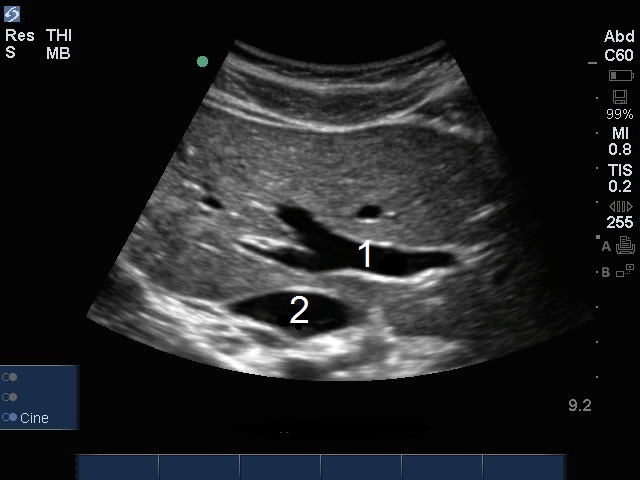

肝脏门静脉图像

门静脉 (PV)

下腔静脉 (IVC)